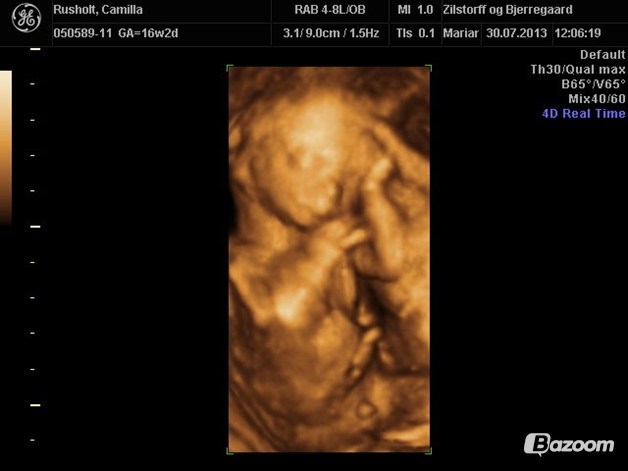

Ja, eller jeg var til scanning 15+5 :-)

Vedhæftede fotos (klik for at se i fuld størrelse)